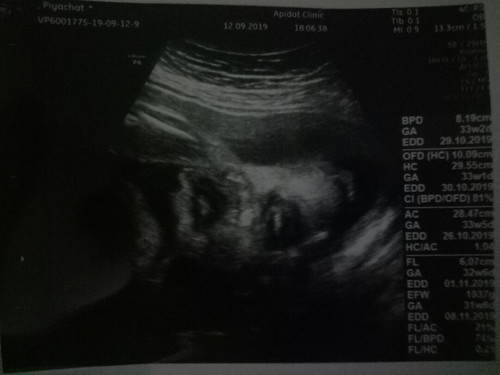

ภาพซาว2มิติ

ทำไมปากน้องใหญ่จังคะ หรือภาพ3มิติก็เป็นแบบนี้ ???

ดู​ตอนกี่วีค?